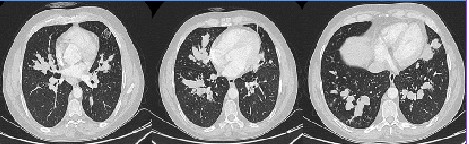

In most cases, asthma precedes vasculitis, and there is a considerable interval between the two.5 Although asthma may improve with the development of vasculitis, it often re-emerges as a significant clinical problem in the post-vasculitis period.2 In our case, there were no active symptoms or findings related to asthma at the time of presentation, but there was a history of asthma. The lung is the most commonly affected organ in CSS, and pulmonary infiltration seen in approximately 90% of patients is one of the 6 ACR criteria used in the diagnosis of CSS.5,9 Usually, transient, patchy or widespread parenchymal changes or nodules have been reported.9 High- resolution computed tomography of the chest in our case revealed widespread, small micronodular parenchymal lesions. Due to the lack of large randomized, controlled trials comparing different treatment methods for the disease, determining the optimal treatment is challenging.10 While corticosteroids provide dramatic improvement, in cases with severe multisystem involvement, cyclophosphamide and daily prednisone treatment are recommended.10 In our case, five of the ACR criteria were present, and the gold standard, biopsy, was applied. The etiology is not fully explained, but it is considered secondary to Aspergillus, as the patient’s symptoms were highlighted due to the decrease in steroid treatment. Corticosteroids are used in treatment and, in cases of insufficient response or the presence of serious side effects related to corticosteroids, drugs such as cyclophosphamide, methotrexate, or azathioprine may be added. We initiated cyclophosphamide treatment in our case, and follow-ups are ongoing.

Figure 1. Dilated bronchi filled with high-density mucus in a central distribution throughout all lobes of both lungs.